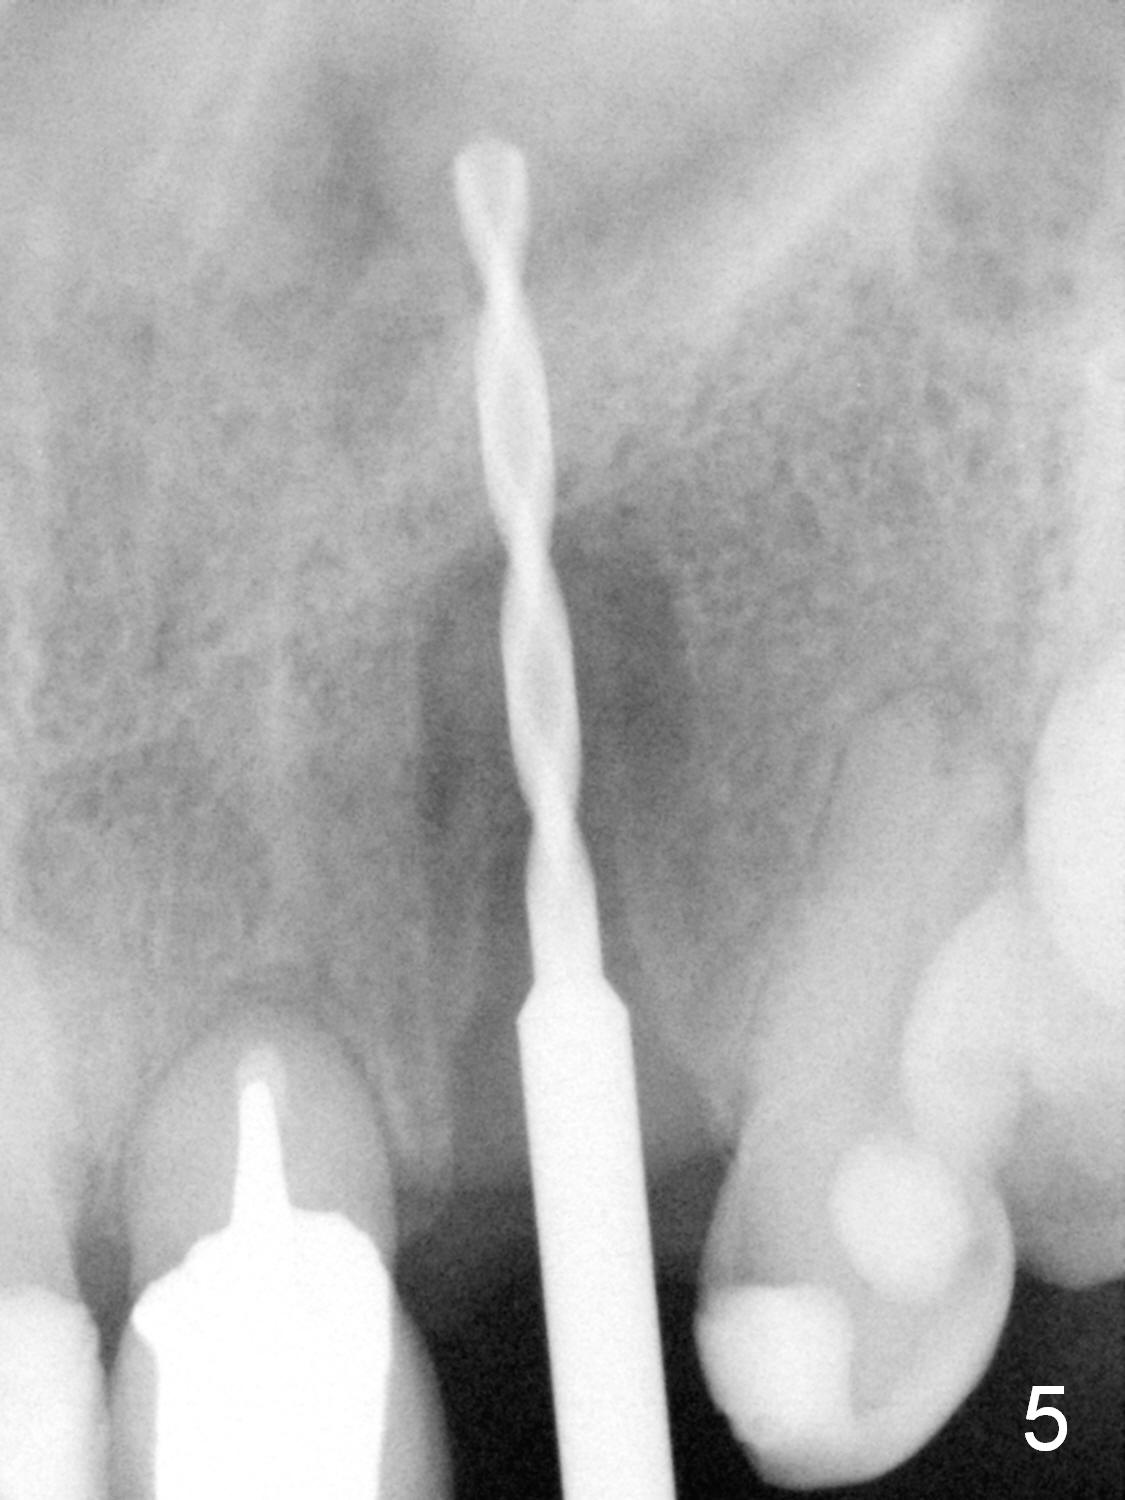

The 57-year-old lady does not like the crown at the site of #10 immediately when it is cemented (Fig.1). When the upper lip is retracted, it appears that the implant is immediately underneath the gingiva (Fig.2 *). It is slightly tender when palpated. The patient refuses CBCT. When the buccal flap is raised, the implant is found to be exposed buccally (Fig.3). When it is removed, the coronal portion of the palatal wall is thin (Fig.4). It appears that there is bone in the mid and apical thirds of the palatal wall, where an osteotomy is initiated using a 1.2 mm pilot drill. When the latter reaches 18 mm from the crest, the nasal floor appears to be perforated. The latter is confirmed by PA (Fig.5). As the osteotomy are increasing in diameter, force is applied as palatally as possible without perforating the palatal wall too much. When a 3.5x20 mm implant is placed (30 Ncm), it is palatal to the labial wall. The defect is filled by allograft and Osteogen, covered by long termed resorption membrane. The buccal flap is sutured (Fig.7). A proposal to place gingival graft is rejected. The implant is shown to have been positioned more or less normally (Fig.8). A removable temporary appliance is fabricated. Periodontal dressing is applied.